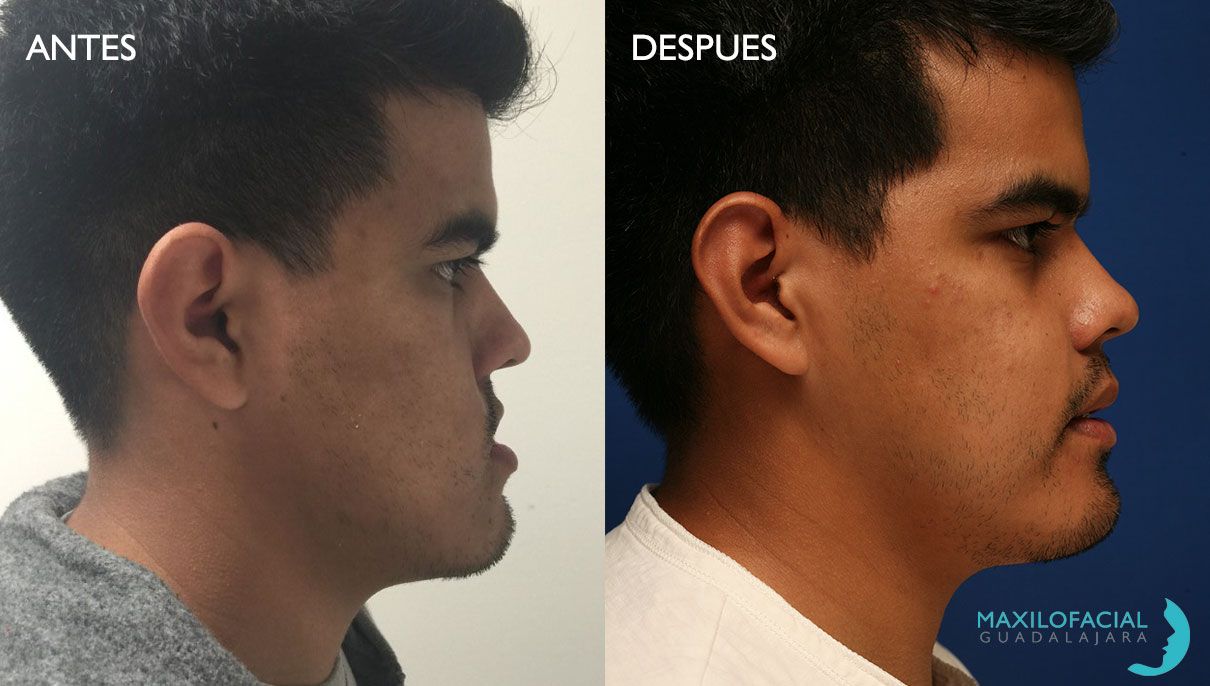

Masculinización Facial

La cirugía de masculinización facial es un conjunto de procedimientos quirúrgicos diseñados para ayudar a personas asignadas femeninas al nacer a lograr una apariencia facial más masculina. Este tipo de cirugía plástica se realiza comúnmente en personas transgénero o no binarias que desean alinear su apariencia facial con su identidad de género masculina.

Es importante señalar que la decisión de someterse a cirugía de masculinización facial es personal y única para cada individuo. Antes de realizar cualquier tipo de cirugía, se recomienda consultar con un equipo médico experimentado en cirugía de género y discutir las opciones disponibles, los riesgos y beneficios, así como las expectativas realistas del resultado.

Masculinización Facial

La cirugía de masculinización facial es un conjunto de procedimientos quirúrgicos diseñados para ayudar a personas asignadas femeninas al nacer a lograr una apariencia facial más masculina. Este tipo de cirugía plástica se realiza comúnmente en personas transgénero o no binarias que desean alinear su apariencia facial con su identidad de género masculina.

Es importante señalar que la decisión de someterse a cirugía de masculinización facial es personal y única para cada individuo. Antes de realizar cualquier tipo de cirugía, se recomienda consultar con un equipo médico experimentado en cirugía de género y discutir las opciones disponibles, los riesgos y beneficios, así como las expectativas realistas del resultado.